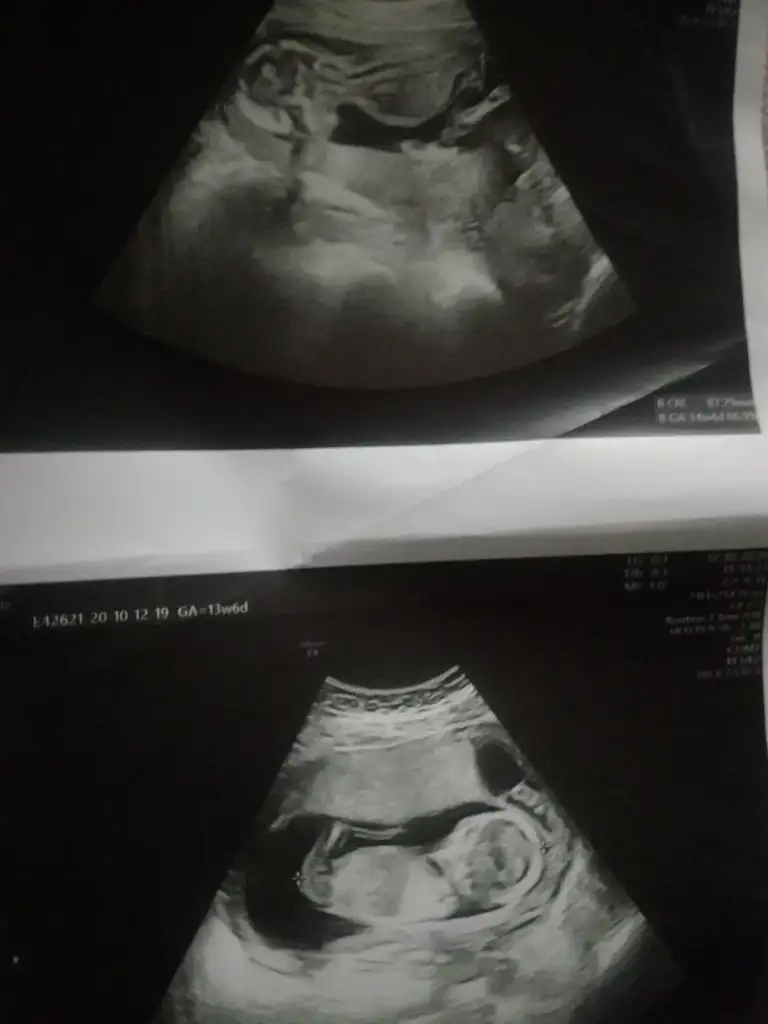

Kız gibi sanki 14 haftada nub olmaz ama sanki diklik olsa yada pipi olsa görünürdüEki Görüntüle 2703543 14 Haaftalık şuan nub a göre yorumlarmısınız

Olursa paylaşın 11 12 13 haftalar olur hiç net değil kız dedim ama olmayabilir net değil ilk bebekmi